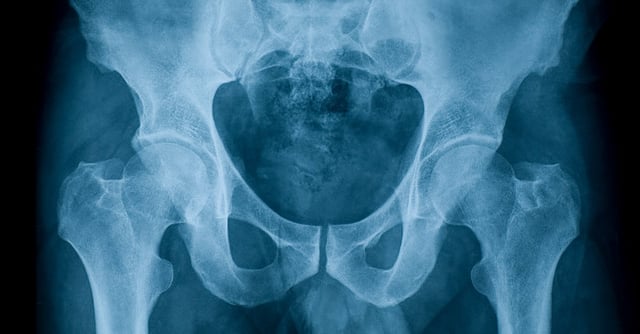

The main reason for hips getting so much attention is simply because it causes so many problems if it luxates (slips out of place), and the risk of that happening is relatively high in people who are not able to stand and walk. Often one and the same person has to deal with all the risk-increasing factors we have mentioned: narrow pelvis, flat acetabulum, femoral neck angled upwards and muscles that is more activated in the direction inward and forward than outward and backward. This creates a situation where the femoral head moves outside the upper edge of the acetabulum over time and eventually ends up outside the joint. This can cause a lot of pain and restrict movement further. As we now know, the hip joint is part of the pelvis, and when the hip is dislocated, the pelvic rim on the same side tilts sharply upwards. This in turn affects the condition of the spine and increases the risk of scoliosis (misalignment of the spine).

So, all the X-rays and measurement of range-of-motion, all adjustments of assistive devices, and all those hours of cogitation – that’s what they’re for! Trying to keep that little ball joint within the confines of the acetabulum so as to keep your child moving and limit pain. Sweden is actually a world leader in preventing hip dislocation, but what does that actually involve? And how do we achieve that?